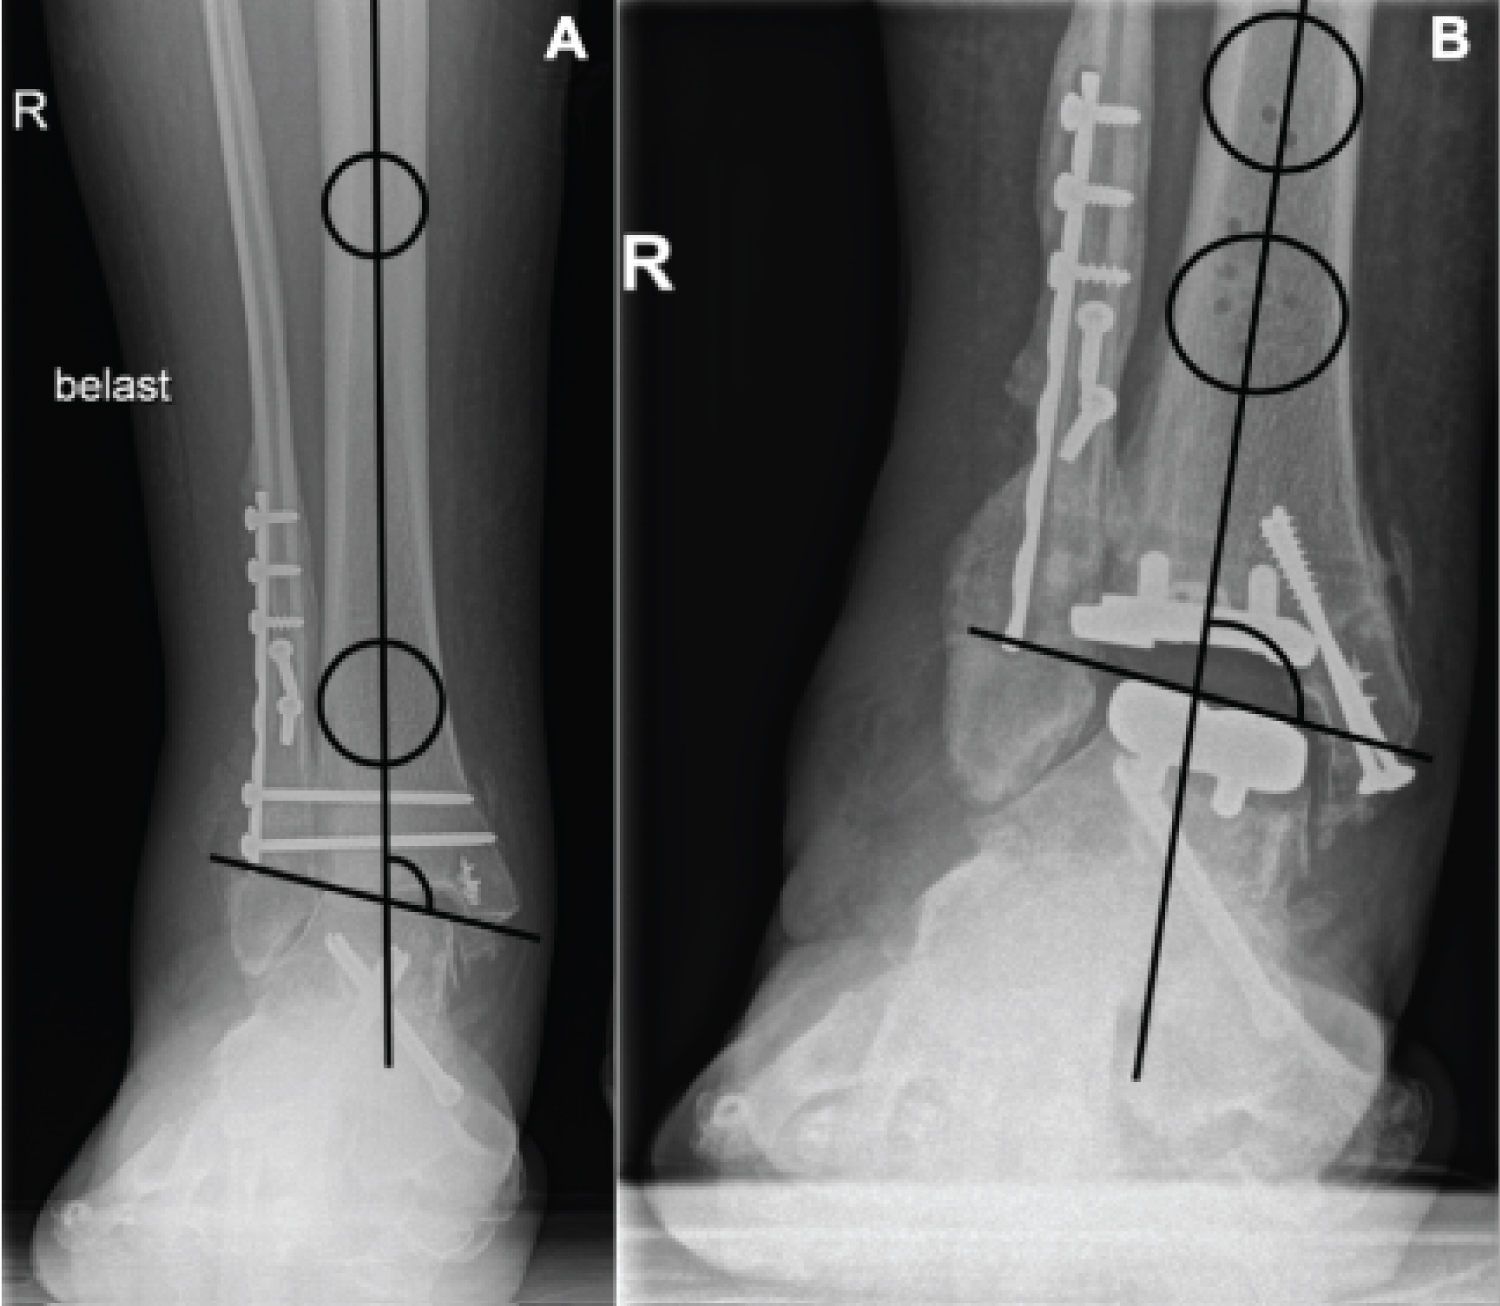

Radiological outcomes were analysed using preoperative and postoperative radiographs in AP and lateral view. Tibial coronal alignment was determined with the medial distal tibial angle (MDTA) and tibial sagittal alignment was determined on the lateral radiograph with the anterior distal tibial angle (ADTA) (Figure 2). The ideal MDTA and ADTA is 90° with a range of 5° [13]. Tibiotalar alignment was determined as the angle between the mechanical axis of the tibia and a line tangential to the talar dome or talar prosthesis component (Figure 3). The ideal angle is 90° with a range of 5° [23]. The talar alignment was determined as the anteroposterior position of the talus in relation to the longitudinal axis of the tibia (Figure 4). When distance x was positive the talus is positioned anteriorly, when distance x was negative the talus is positioned posteriorly [20].

Figure 3: (A) Tibiotalar alignment measured with the angle between the mechanical axis of the tibia and a line tangential to the talar dome in pre-operative setting and; (B) The talar component in postoperative setting. View Figure 3

Preoperatively the tibiotalar alignment ranged from 68.5° to 100.2° with four ankles in the normal range between 85° and 95°. Five ankles had a varus deformity with a mean of 7.6° ± 7.3° and two ankles had a valgus deformity of 0.6° and 5.2° degrees. The postoperative tibiotalar alignment ranged from 81.5° to 106.2° with seven ankles in the normal range. Two ankles had a valgus malalignment of 4.1° and 11.2°, and two ankles had a varus malalignment of 0.7° and 3.5°.

The mean preoperative talar alignment ranged between 0.9 mm to 12.8 mm and was translated anteriorly in all cases. The mean postoperative talar alignment ranged from 0.8 mm to 15.1 mm and was translated anteriorly in all cases. There was no significant difference in preoperative and postoperative tibiotalar and talar alignment (Table 5).